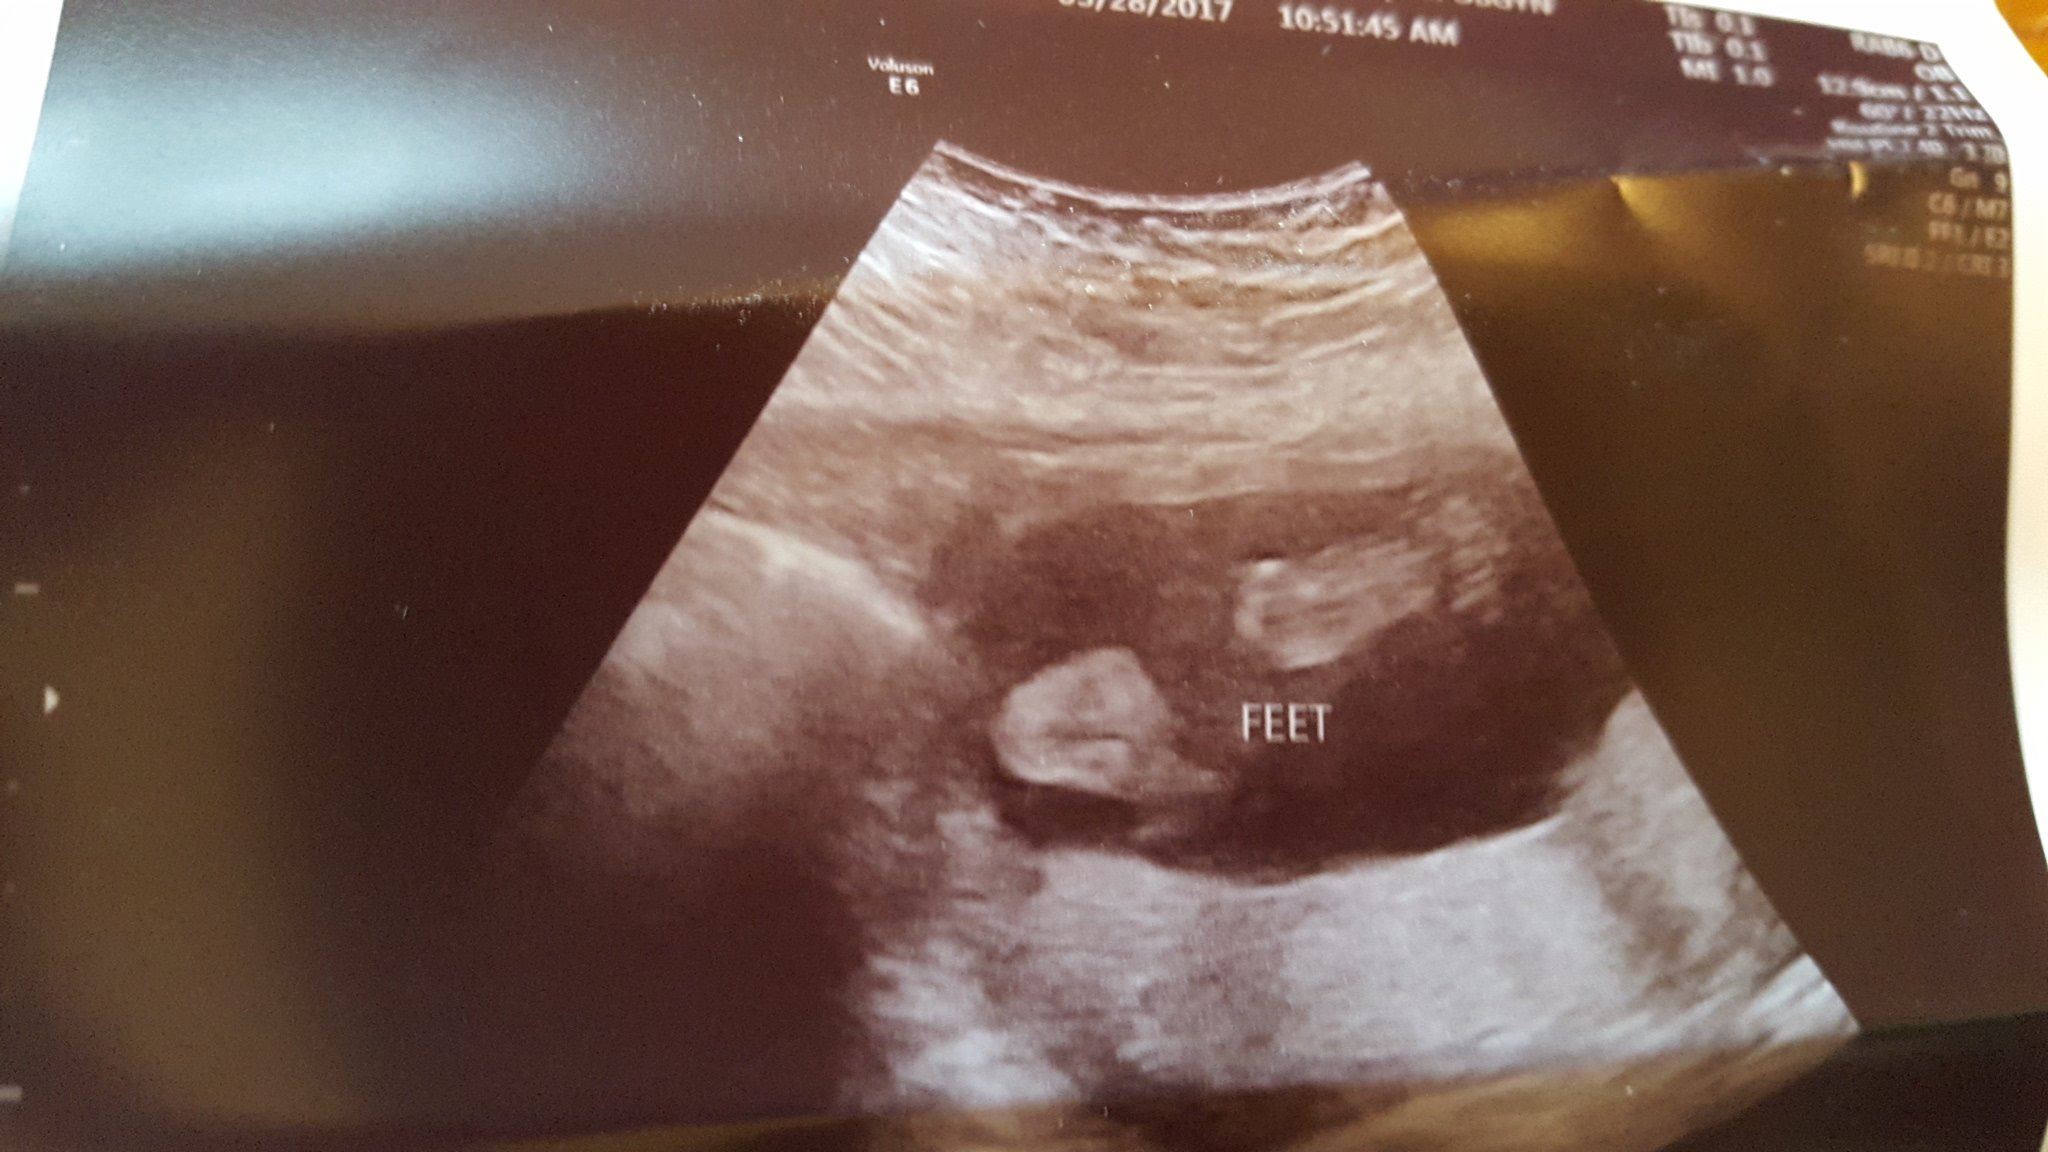

Had our scan today! She was curled in a ball with her hands together in front of her face and her feet crossed most of the time. (DD did the same thing for her scan) They were able to see almost everything but we are going back in 4 weeks to get a better look at anything they couldn't see. They confirmed girl and she weighed in at 11oz!